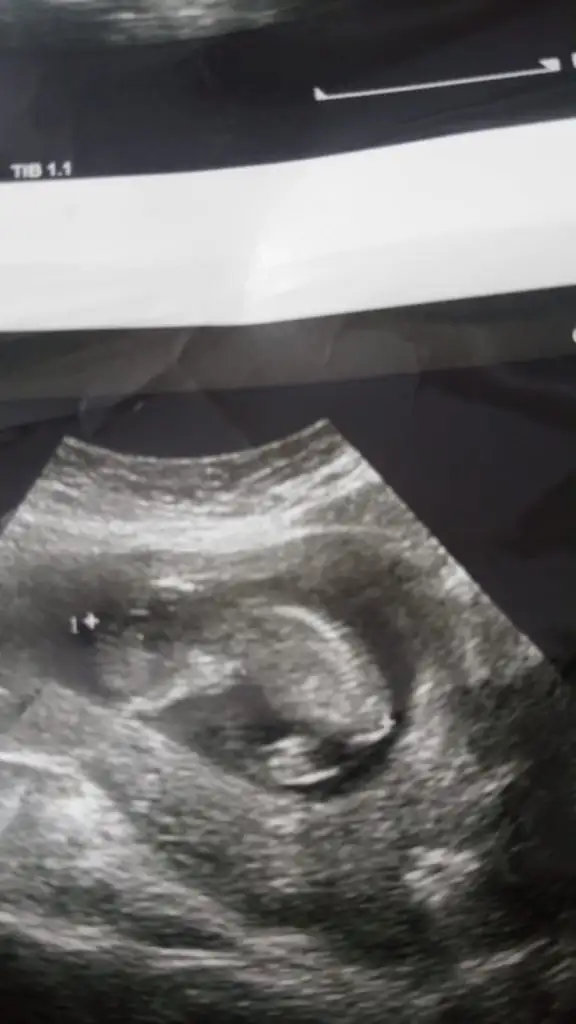

Bizede bakabilirmisiniz acaba 18.haftaya girdik daha cinsiyetimizi öğrenemedik yardımcı olursanız seviniriz 😊

Nubu erkek gibi canım kaç haftalıkta benzetti hayırlısı olsun sizin için başka usg varmı zorladım çünki usg tam net degil yakınlaştırınca puslanıyor usg minik çünki 😊

Ayda bir gidiyorum diğer ultrason görüntüsü 8 haftalık ordan anlaşılmaz diye düşünüyorum.işte 12.haftada cumartesi günü gittigimde doktor pek emin değilim bacak arasını pek göremedim değişebilir ama kız gibi dedi.telefonumun arka kamerası bozuk onle çekiyorum o da çok net çekmiyor size daha yakın bi foto atayım net değilse sonra eşimin teliyle çekerim çünkü başka ultrason görüntüsü yok maalesef. Belki kafa yapısı ile ilgili de bi tahmininiz olur .

Evet net degil kafa şeklide erkek gibi tekrar paylaşın net bir usg cnm 😊